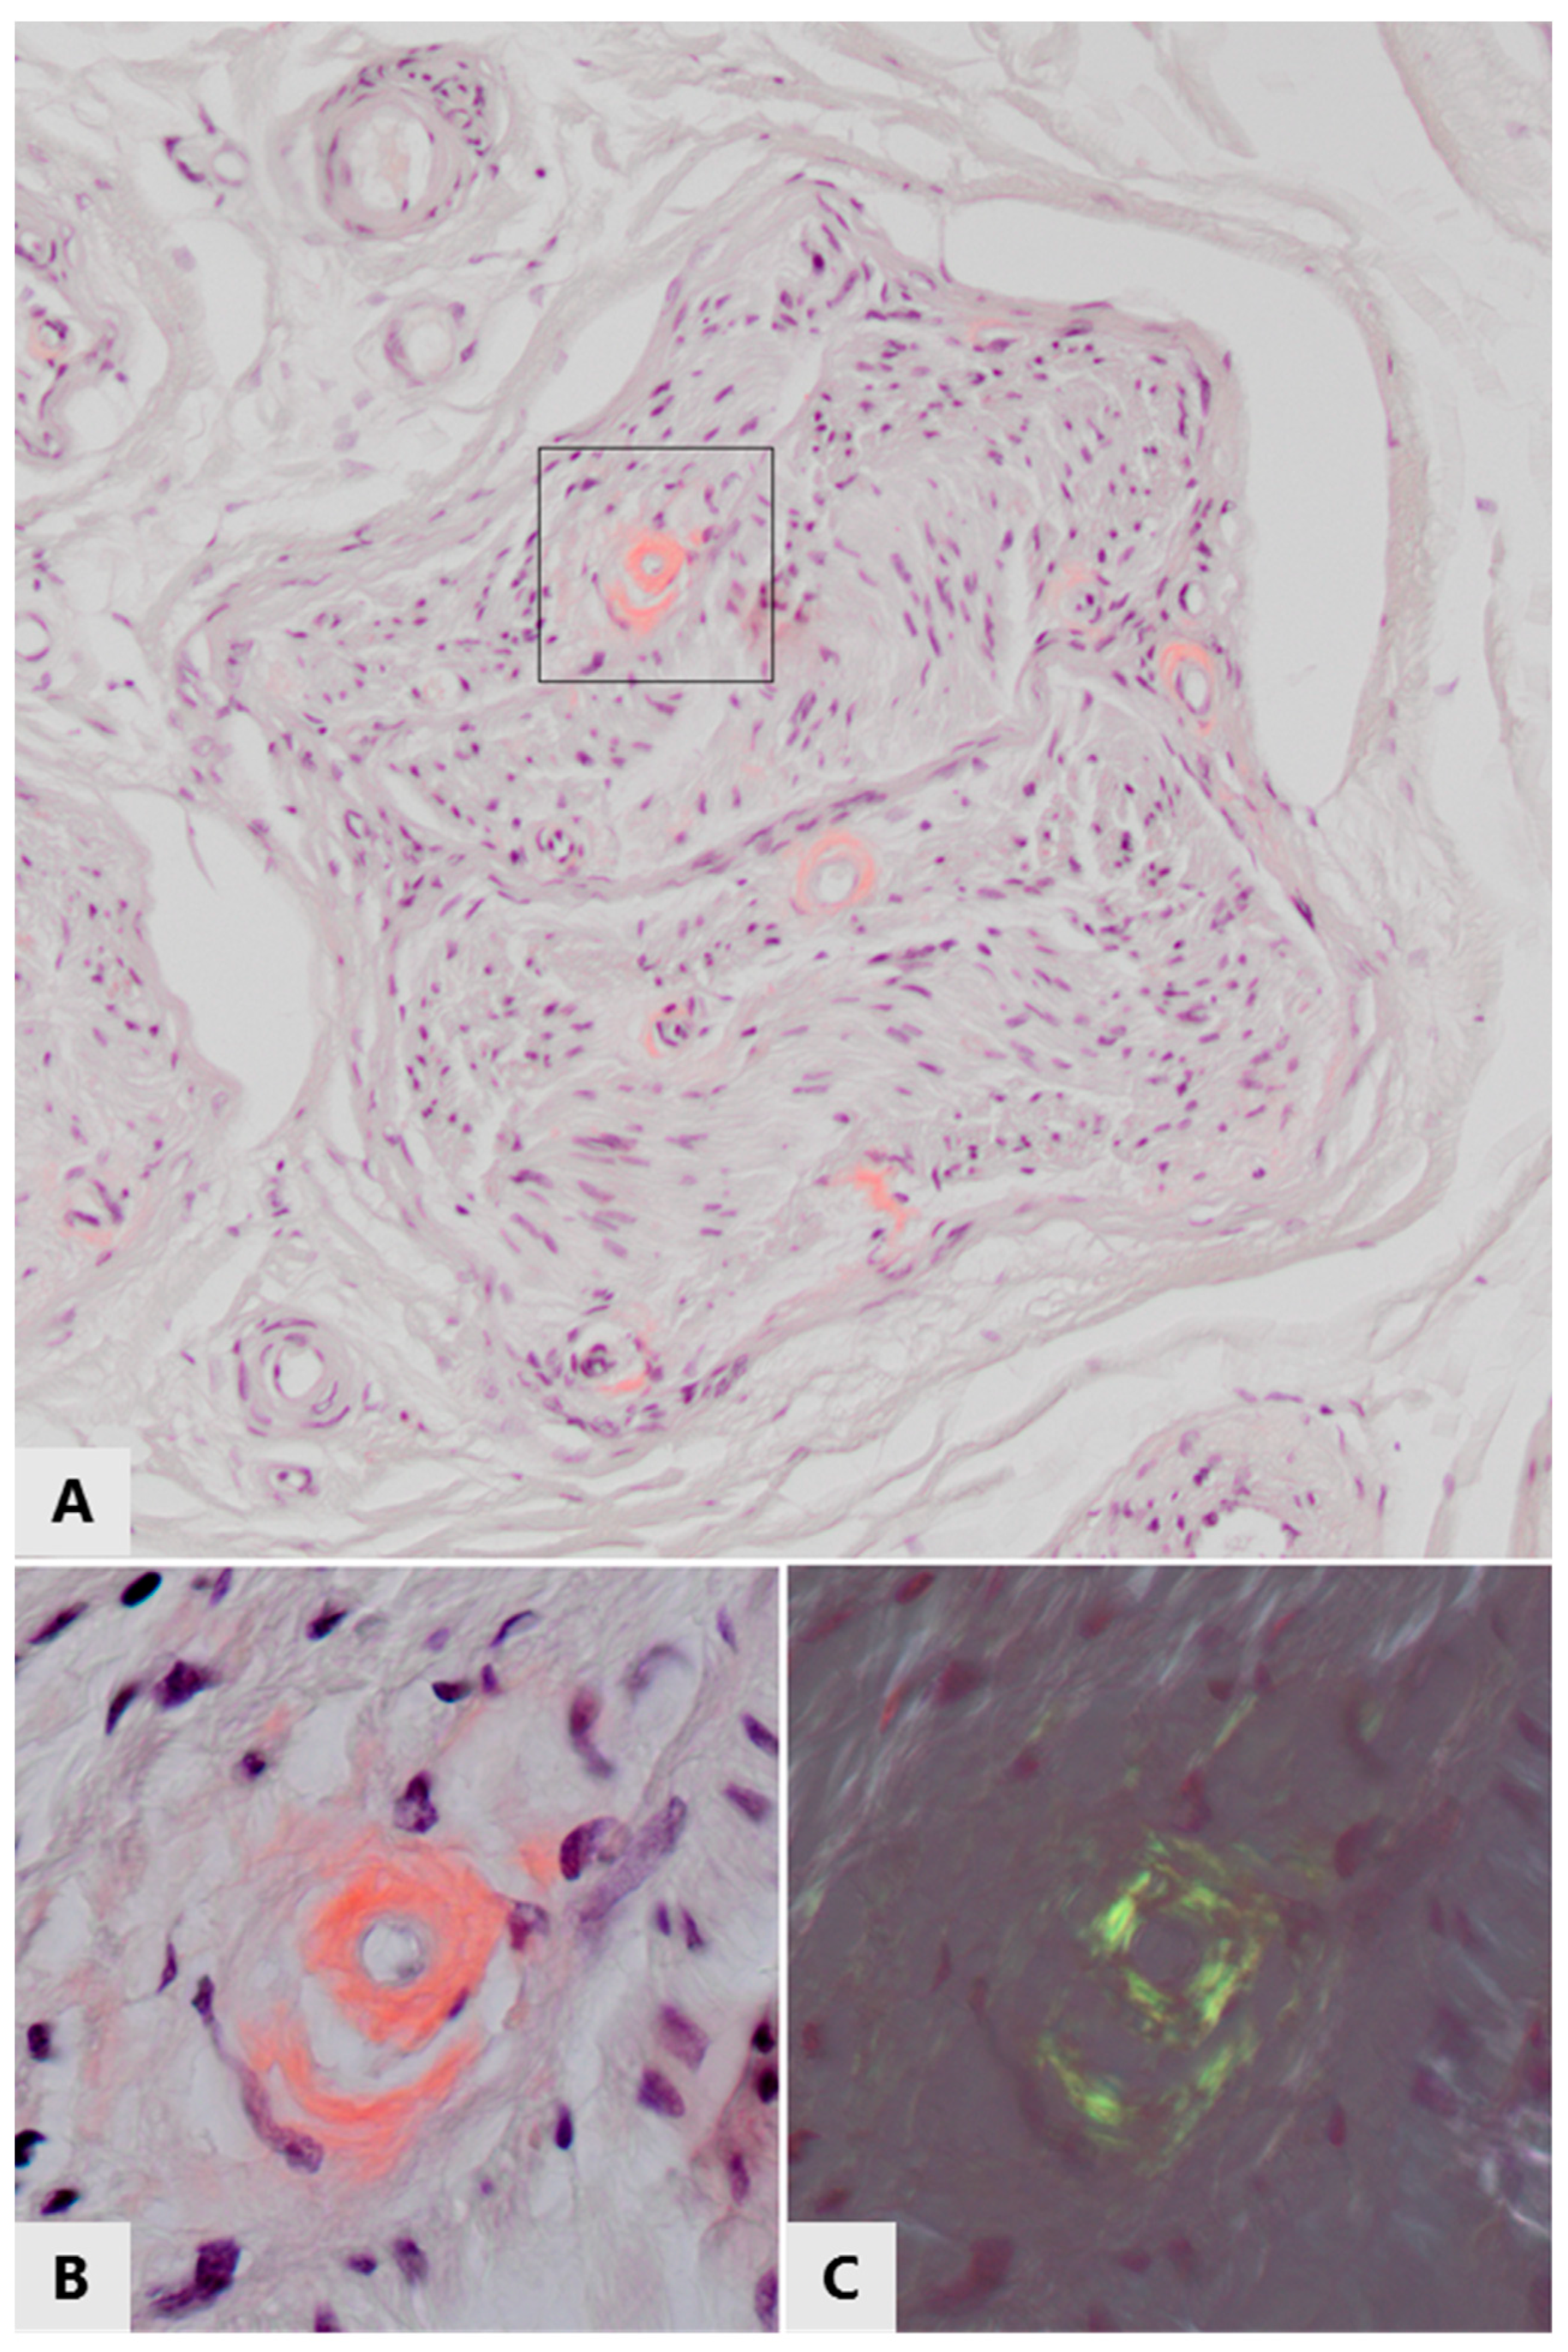

- Vital, C.; Vital, A.; Bouillot-Eimer, S.; Brechenmacher, C.; Ferrer, X.; Lagueny, A. Amyloid neuropathy: A retrospective study of 35 peripheral nerve biopsies. J. Peripher. Nerv. Syst. 2004, 9, 232–241. [Google Scholar] [CrossRef]